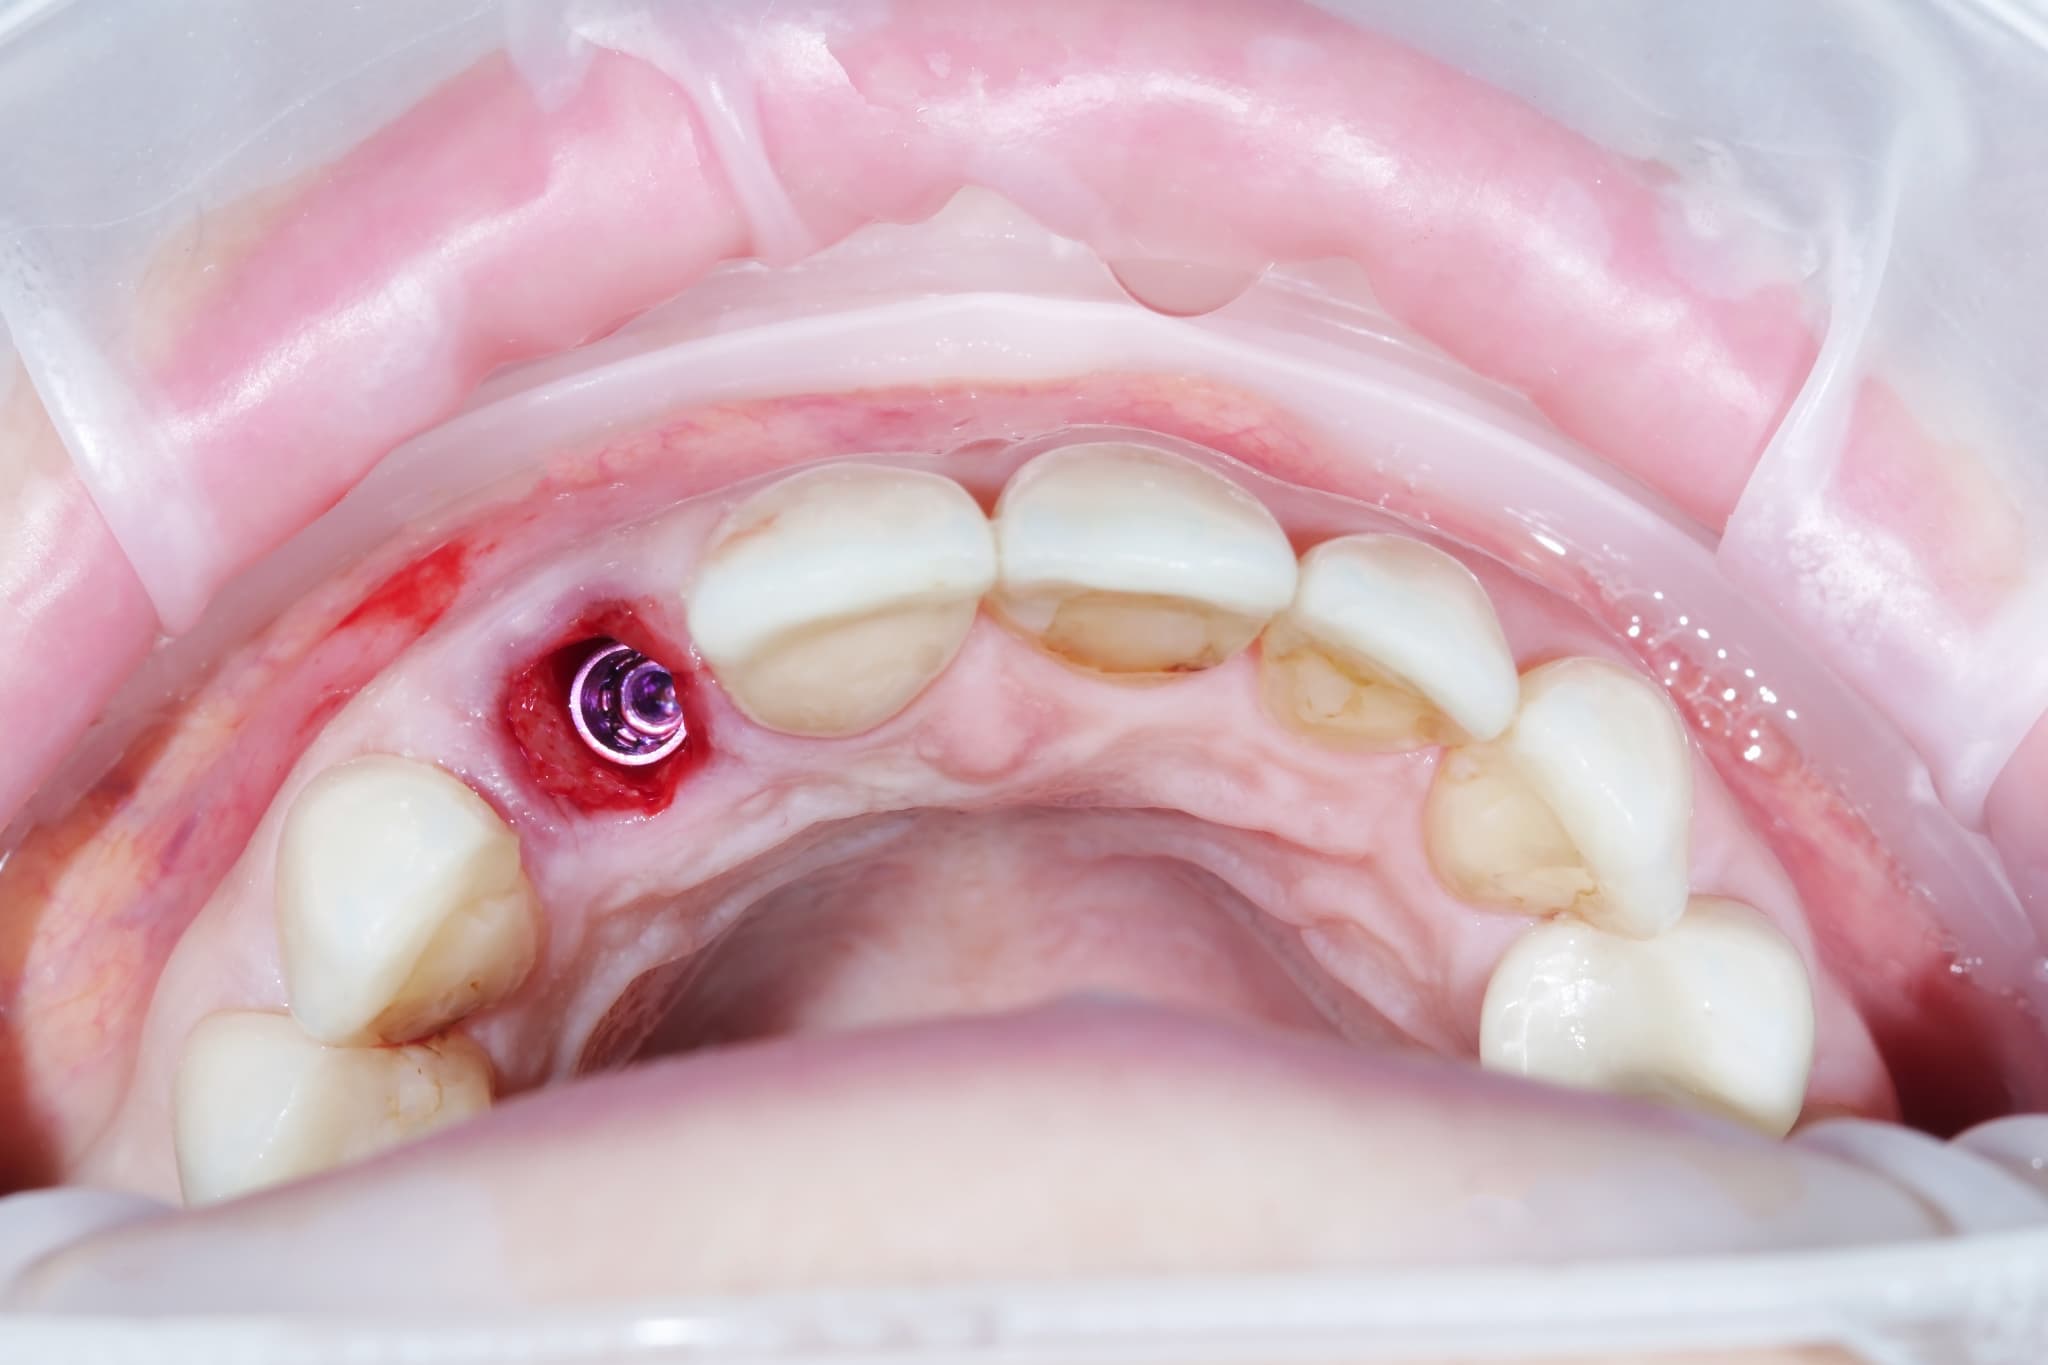

インプラント周囲炎になった歯茎

インプラント周囲炎とは、インプラントを支える骨や周囲の組織に炎症が生じる状態を指します。インプラントの周囲に細菌が繁殖し、歯ぐきの腫れや出血、さらに進行すると骨が溶けてしまうこともあります。

初期には自覚症状が少ないため、気づかないうちに進行することがある点に注意が必要です。